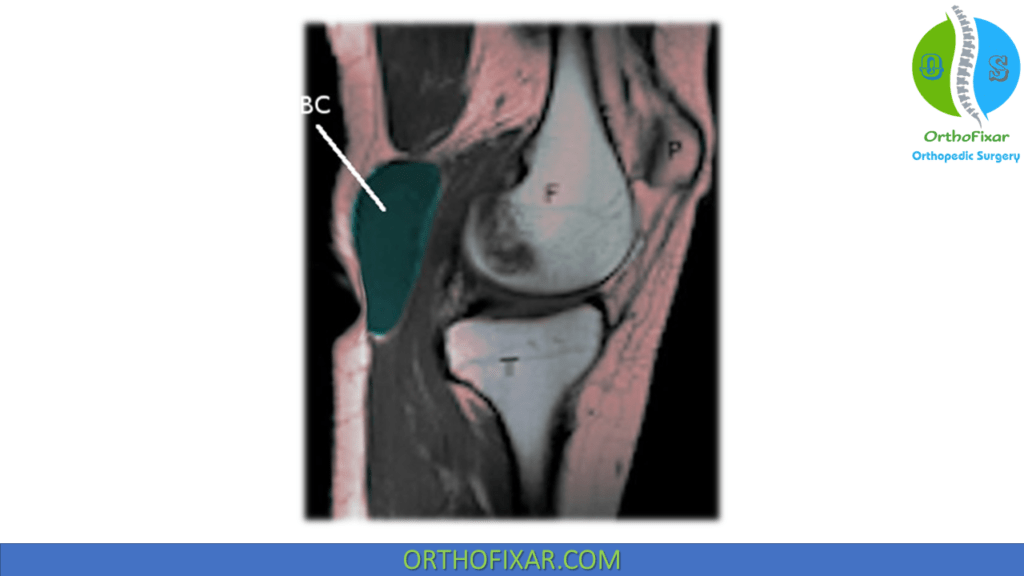

From orthofixar.com

Baker's Cyst Aspiration OrthoFixar 2024 Baker's Cyst Vs Clot Baker's cyst typically appears as a single or multiple lump with clearly defined borders, covered by normal skin without discoloration. Clinically and historically, one cannot differentiate this condition from the. It can be hard to tell. It causes a bulge and a feeling of tightness. How do you tell the difference between a baker’s cyst and a dvt blood clot?. Baker's Cyst Vs Clot.